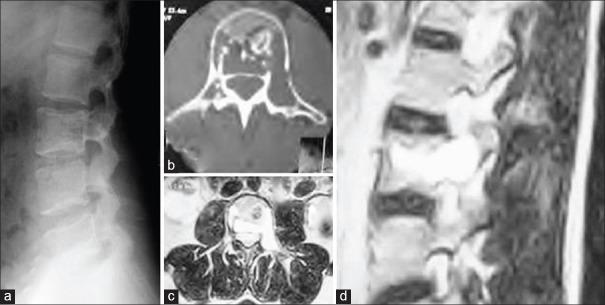

Aneurysmal bone cyst (ABC) is a vascular tumor of the spine. Management of spinal ABC still remains controversial because of its location, vascular nature and incidence of recurrence. In this manuscript, we hereby describe two cases of ABC spine treated by curettage, vertebral cement augmentation for control of bleeding and internal stabilization with two years followup. To the best of our knowledge, this is the first case report in the literature describing the role of cement augmentation in spinal ABC in controlling vascular bleeding in curettage of ABC of spine. Case 1: A 22 year old male patient presented with chronic back pain. On radiological investigation, there were multiple, osteolytic septite lesions at L3 vertebral body without neural compression or instability. Percutaneous transpedicular biopsy of L3 from involved pedicle was done. This was followed by cement augmentation through the uninvolved pedicle. Next, transpedicular complete curettage was done through involved pedicle. Case 2: A 15-year-old female presented with nonradiating back pain and progressive myelopathy. On radiological investigation, there was an osteolytic lesion at D9. At surgery, decompression, pedicle screw-rod fixation and posterolateral fusion from D7 to D11 was done. At D9 level, through normal pedicle cement augmentation was added to provide anterior column support and to control the expected bleeding following curettage. Transpedicular complete curettage was done through the involved pedicle with controlled bleeding at the surgical field. Cement augmentation was providing controlled bleeding at surgical field during curettage, internal stabilization and control of pain. On 2 years followup, pain was relieved and there was a stable spinal segment with well filled cement without any sign of recurrence in computed tomography scan. In selected cases of spinal ABC with single vertebral, single pedicle involvement; cement augmentation of vertebra through normal pedicle has an important role in surgery aimed for curettage of vertebra.

骨动脉瘤样囊肿(ABC)是一种脊柱血管性肿瘤。由于其位置、血管性质和复发率,脊柱ABC的治疗仍存在争议。在本手稿中,我们特此描述了两例经刮除术、椎体骨水泥强化以控制出血并进行内固定治疗的脊柱ABC病例,并进行了两年的随访。据我们所知,这是文献中首例描述骨水泥强化在脊柱ABC刮除术中控制血管出血作用的病例报告。病例1:一名22岁男性患者出现慢性背痛。经影像学检查,L3椎体有多个溶骨性分隔病变,无神经受压或不稳定。对L3受累椎弓根进行了经皮椎弓根穿刺活检。随后通过未受累椎弓根进行骨水泥强化。接下来,通过受累椎弓根进行经椎弓根完全刮除术。病例2:一名15岁女性出现非放射性背痛和进行性脊髓病。经影像学检查,D9有一个溶骨性病变。手术时,进行了减压、椎弓根螺钉-棒固定以及从D7到D11的后外侧融合。在D9水平,通过正常椎弓根添加骨水泥强化以提供前柱支撑并控制刮除术后预期的出血。通过受累椎弓根进行经椎弓根完全刮除术,手术野出血得到控制。骨水泥强化在刮除术、内固定和疼痛控制过程中为手术野提供了出血控制。经过两年随访,疼痛缓解,脊柱节段稳定,骨水泥填充良好,计算机断层扫描未显示任何复发迹象。在选定的单椎体、单椎弓根受累的脊柱ABC病例中,通过正常椎弓根进行椎体骨水泥强化在旨在刮除椎体的手术中具有重要作用。